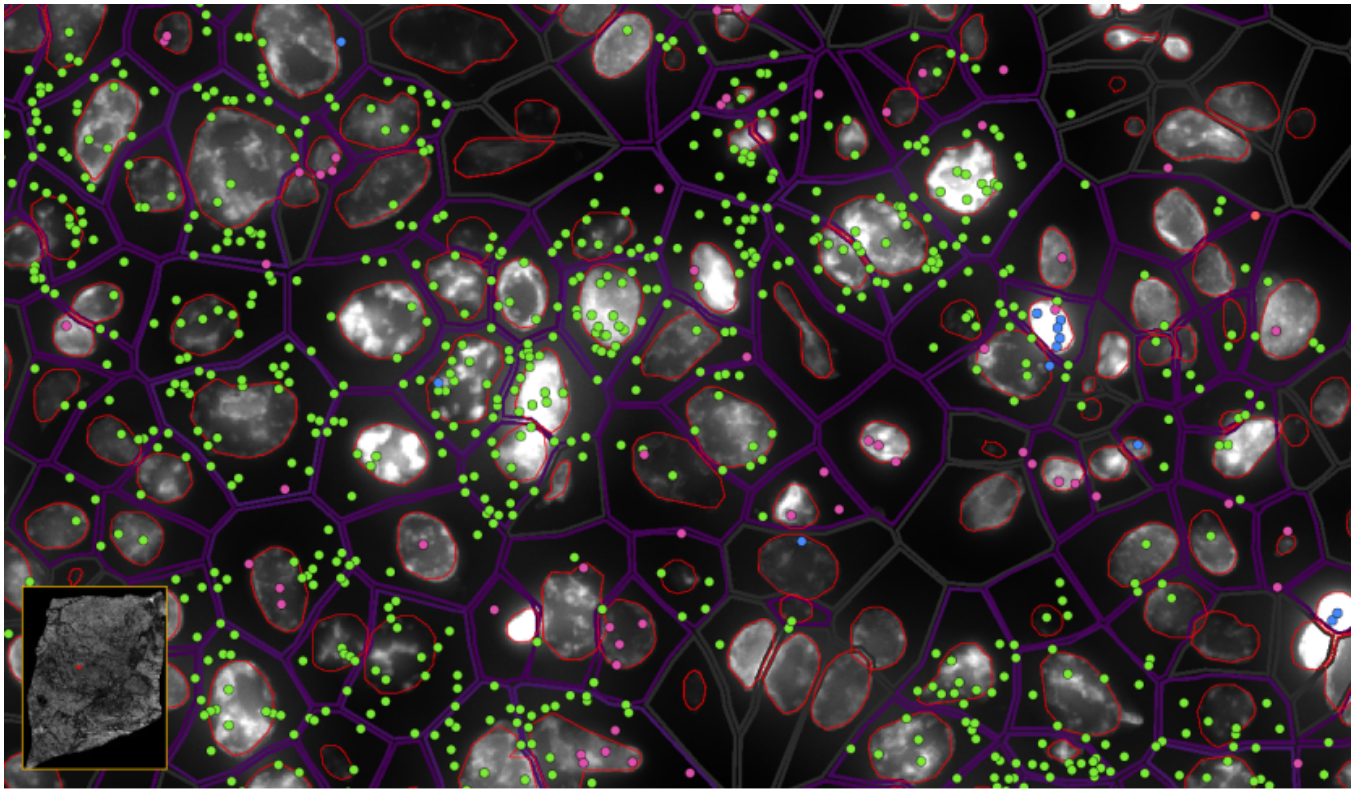

ͼ6-1£ºÊµÏÖµ¥Ï¸°û/ÑÇϸ°ûÇø·ÖÂʵĿռäת¼×éÆÊÎö£¬£¬£¬£¬£¬£¬£¬Â̵ã-EPCAM , À¶µã-KLRD1 £¬£¬£¬£¬£¬£¬£¬·Ûºìµã-LILRB2

ͼ6-2£ºÊµÏÖµ¥Ï¸°û/ÑÇϸ°ûÇø·ÖÂʵĿռäת¼×éÆÊÎö£¬£¬£¬£¬£¬£¬£¬Â̵ã-EPCAMת¼±¾